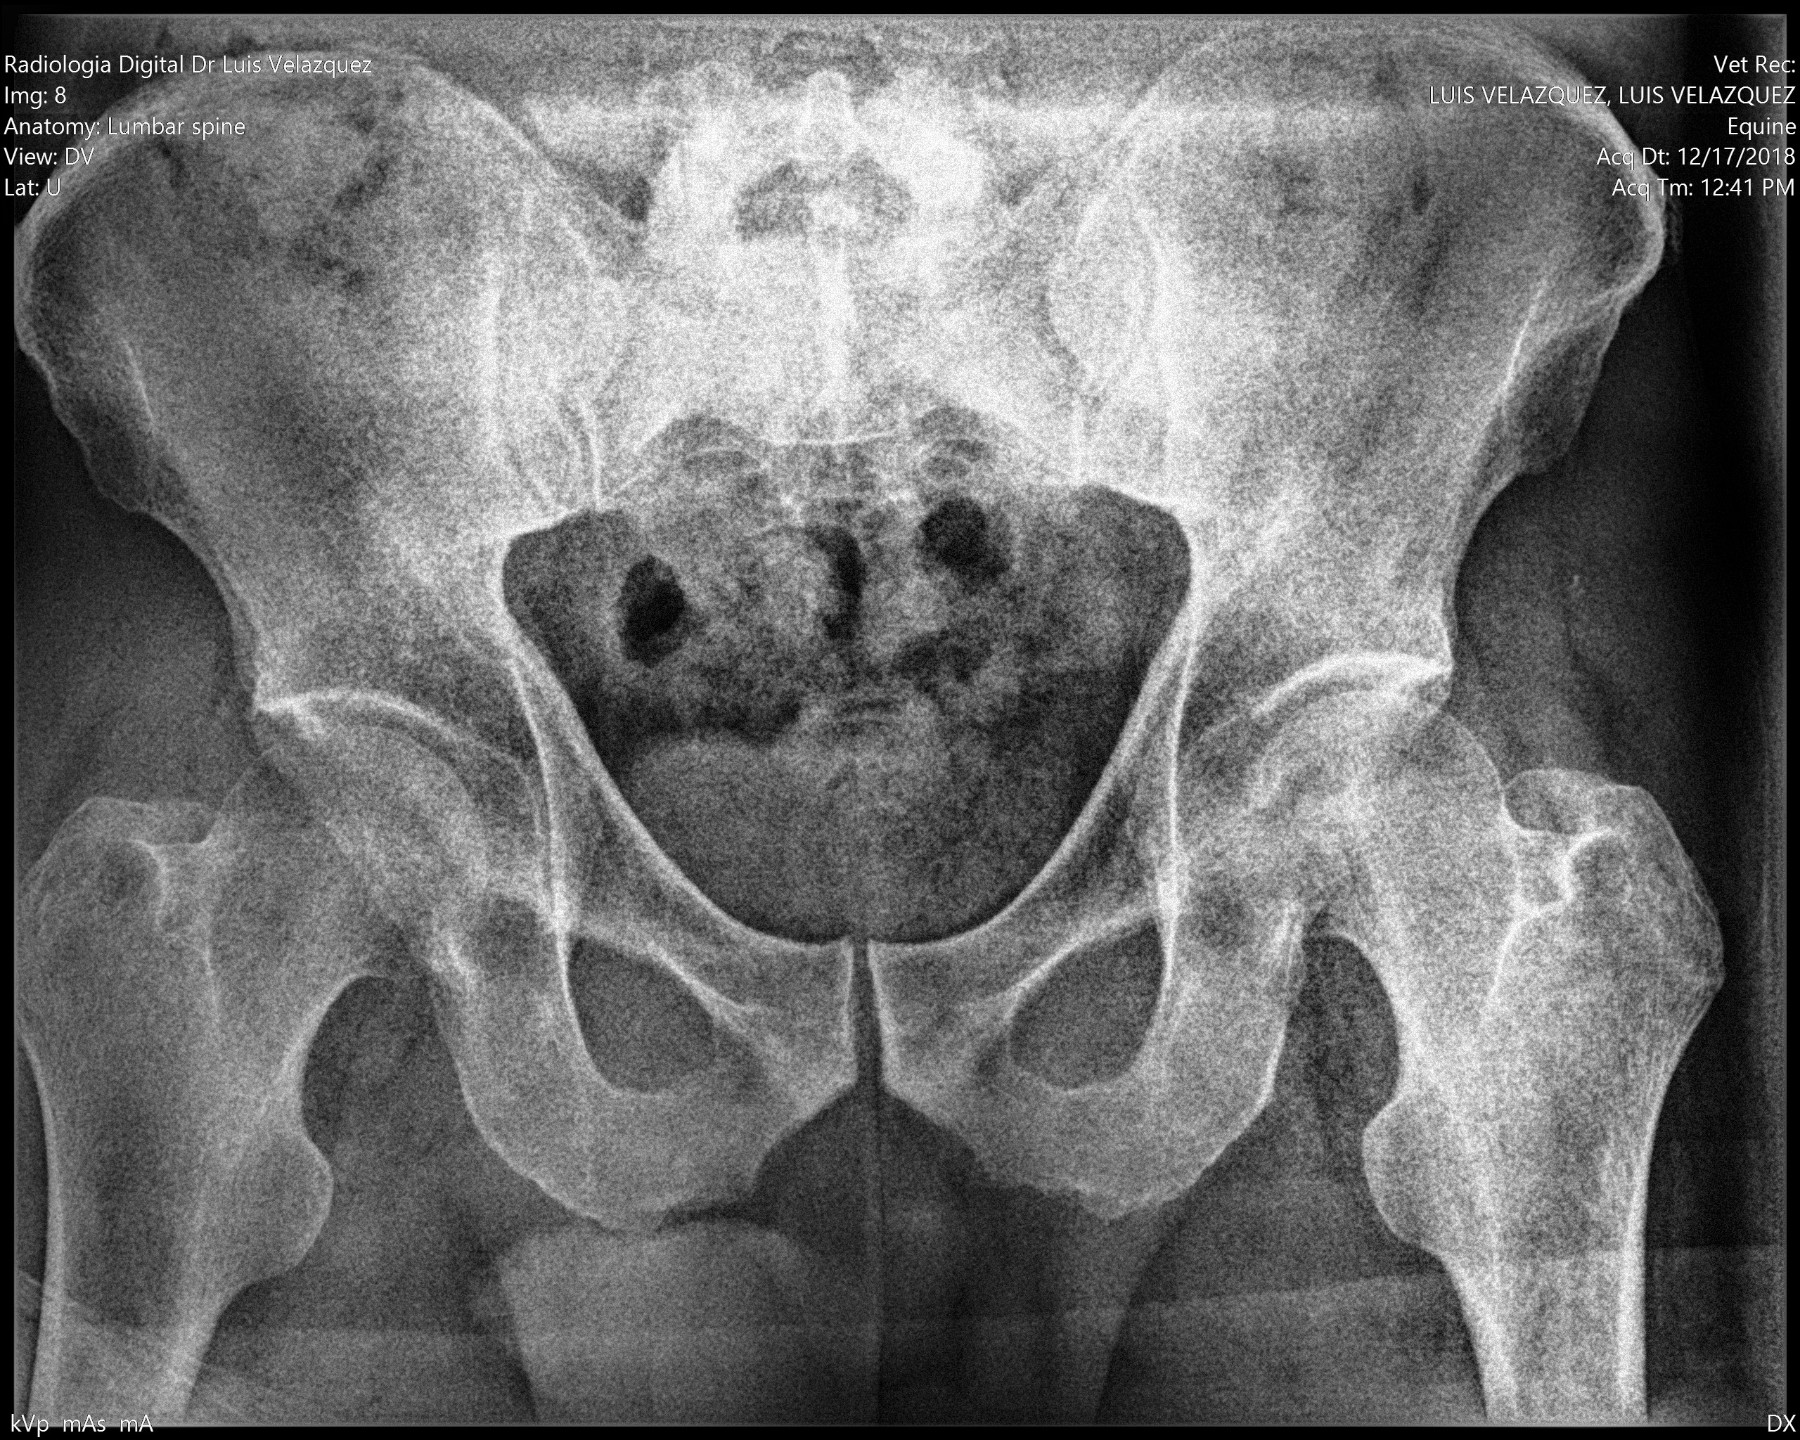

Radiología Digital como Herramienta Complementaria en el Dictamen de Bienes Muebles